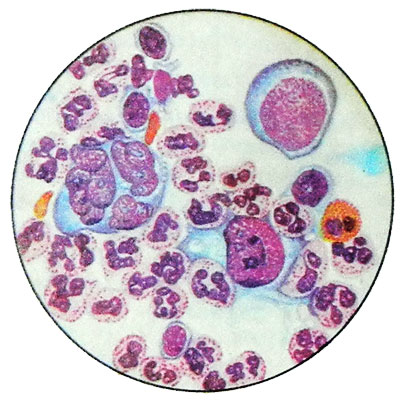

Микропрепараты: Лимфогранулематоз и Нодулярный Склероз